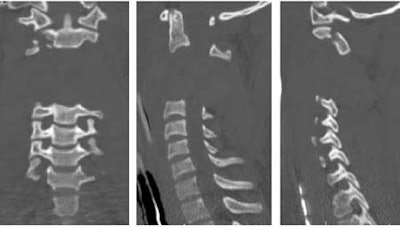

"We obtain a portable lateral spine film in the trauma room first to get an initial view of the airway and cervical spine, then we do MDCT, and if no fracture is seen we take an out-of-collar lateral c-spine film in the trauma center," to look for any instability, Novelline said.

MDCT images are acquired over 25 seconds using 2.5-mm slice thickness, 2.5-mm image spacing, HQ mode. MDCT images are reconstructed to 1.25-mm slice thickness, 1-mm image spacing. Sagittal and coronal reformations are created using 2.5-mm slices and 2.5-mm spacing.

![]() |